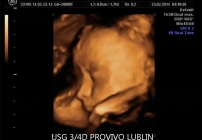

BADANIE USG 3/4D umożliwa dokładny wgląd w rozwój płodu, pozwala na podglądnięcie dziecka w sposób niemalże identyczny z jego aktualnym wyglądem.